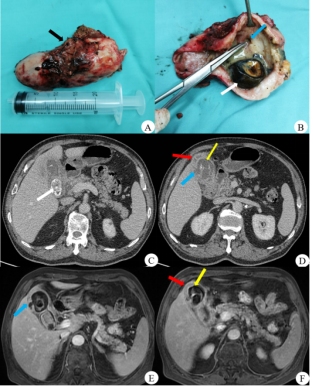

A图:手术大体标本显示胆囊壁毛糙(黑箭);B图:胆囊剖面图,胆囊腔内结石(白箭)和局部胆囊壁不连续(蓝箭);C图:胆囊腔内混杂密度结石(白箭);D & F图:胆囊浆膜层(红箭)和黏膜层(黄箭)明显强化,二者间低强化区为肌层,三者构成“夹心饼干”征;D & E图:胆囊黏膜层局部连续性中断(蓝箭),提示胆囊局部穿孔。